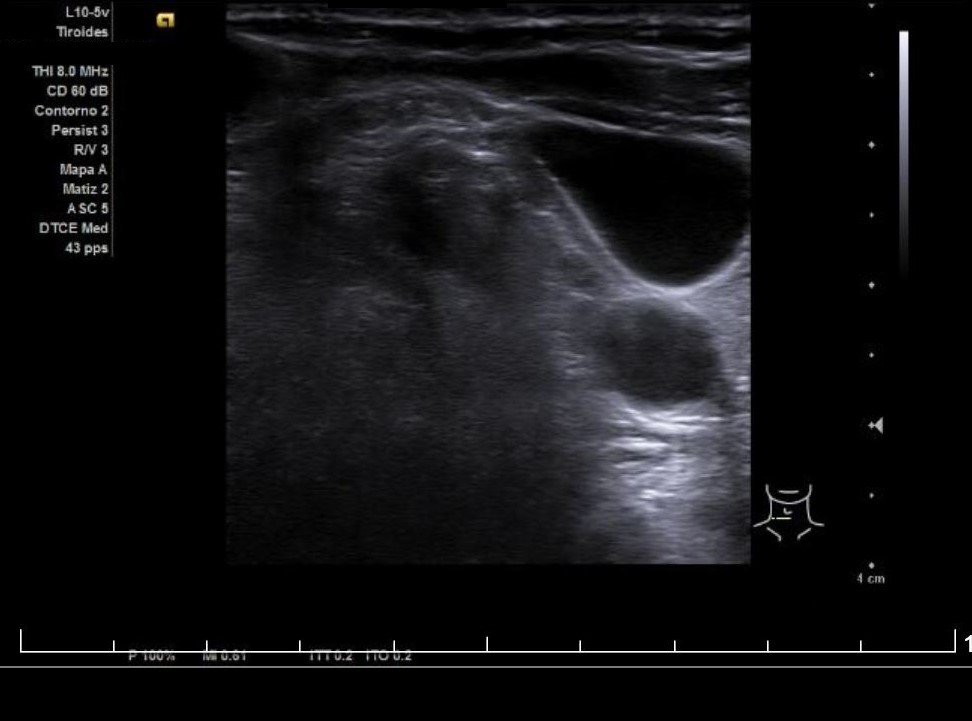

Se aprecia un tiroides de características ecográficas compatibles con tiroiditis, sin cambios respecto a ecografía previa, al igual que la grasa peritiroidea derecha, pero de manera incidental se observa un aumento del calibre fusiforme de la yugular externa derecha con respecto a la izquierda, con flujo vascular reducido.

Ante la sospecha clínica y ecográfica de trombosis o flebectasia yugular se derivó a la paciente a urgencias, donde se realizó una ecografía reglada informada como normal, además de Eco-Doppler de troncos supraórticos también informada como normal.